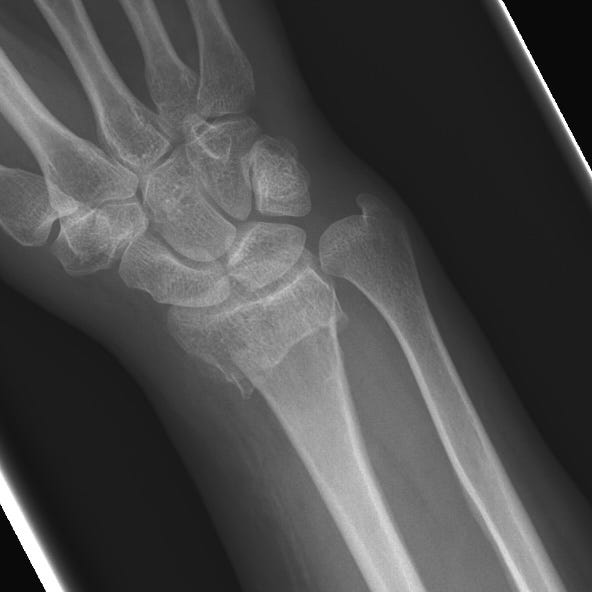

Distal Radial Fractures Pdf Skeletal System Musculoskeletal Distal radius fractures are classified according to (1) extension into the radiocarpal joint, (2) extension to the distal radioulnar articulation, and (3) the presence of an associated ulnar styloid fracture. Distal radius fractures are the most common orthopaedic injury and generally result from fall on an outstretched hand.

Distal Radial Fractures By Alexander Baxter Radnotes Acute distal radius fracture results in pain, tenderness, swelling and potential deformity. patients may be faced with substantial morbidity if fracture healing is delayed or results in clinically significant deformity. Distal radius fractures, commonly known as a wrist fracture, are defined by the involvement of the metaphysis of the distal radius. in younger patients, they are commonly associated with high energy mechanisms, and in older patients, they more frequently occur with lower energy mechanisms or falls. Common distal radial fractures home uw emergency radiology trauma radiology reference resource 09. upper extremity common distal radial fractures page views: 15,253. In this report, we have summarized the evidence on treatment and rehabilitation of distal radial fractures from the most recent available systematic reviews of high quality.

Distal Radial Fractures By Alexander Baxter Radnotes Common distal radial fractures home uw emergency radiology trauma radiology reference resource 09. upper extremity common distal radial fractures page views: 15,253. In this report, we have summarized the evidence on treatment and rehabilitation of distal radial fractures from the most recent available systematic reviews of high quality. Distal radial fractures are a heterogeneous group of fractures that occur at the distal radius and are the dominant fracture type at the wrist. these common fractures usually occur when significant force is applied to the distal radial metaphysis. A randomized, controlled trial of distal radius fractures with metaphyseal displacement but without joint incongruity: closed reduction and casting versus closed reduction, spanning external fixation, and optional percutaneous k wires. We review the evidence behind each guideline and highlight the practical implications of each guideline on care. This guideline is based upon 6 high quality studies, with 3 comparing different fixation techniques for complete intra articular distal radius fractures (jakubietz, yazdanshenas, hammer) and 3 comparing different fixation techniques for unstable distal radius fractures (marcheix, rozental, goehre).